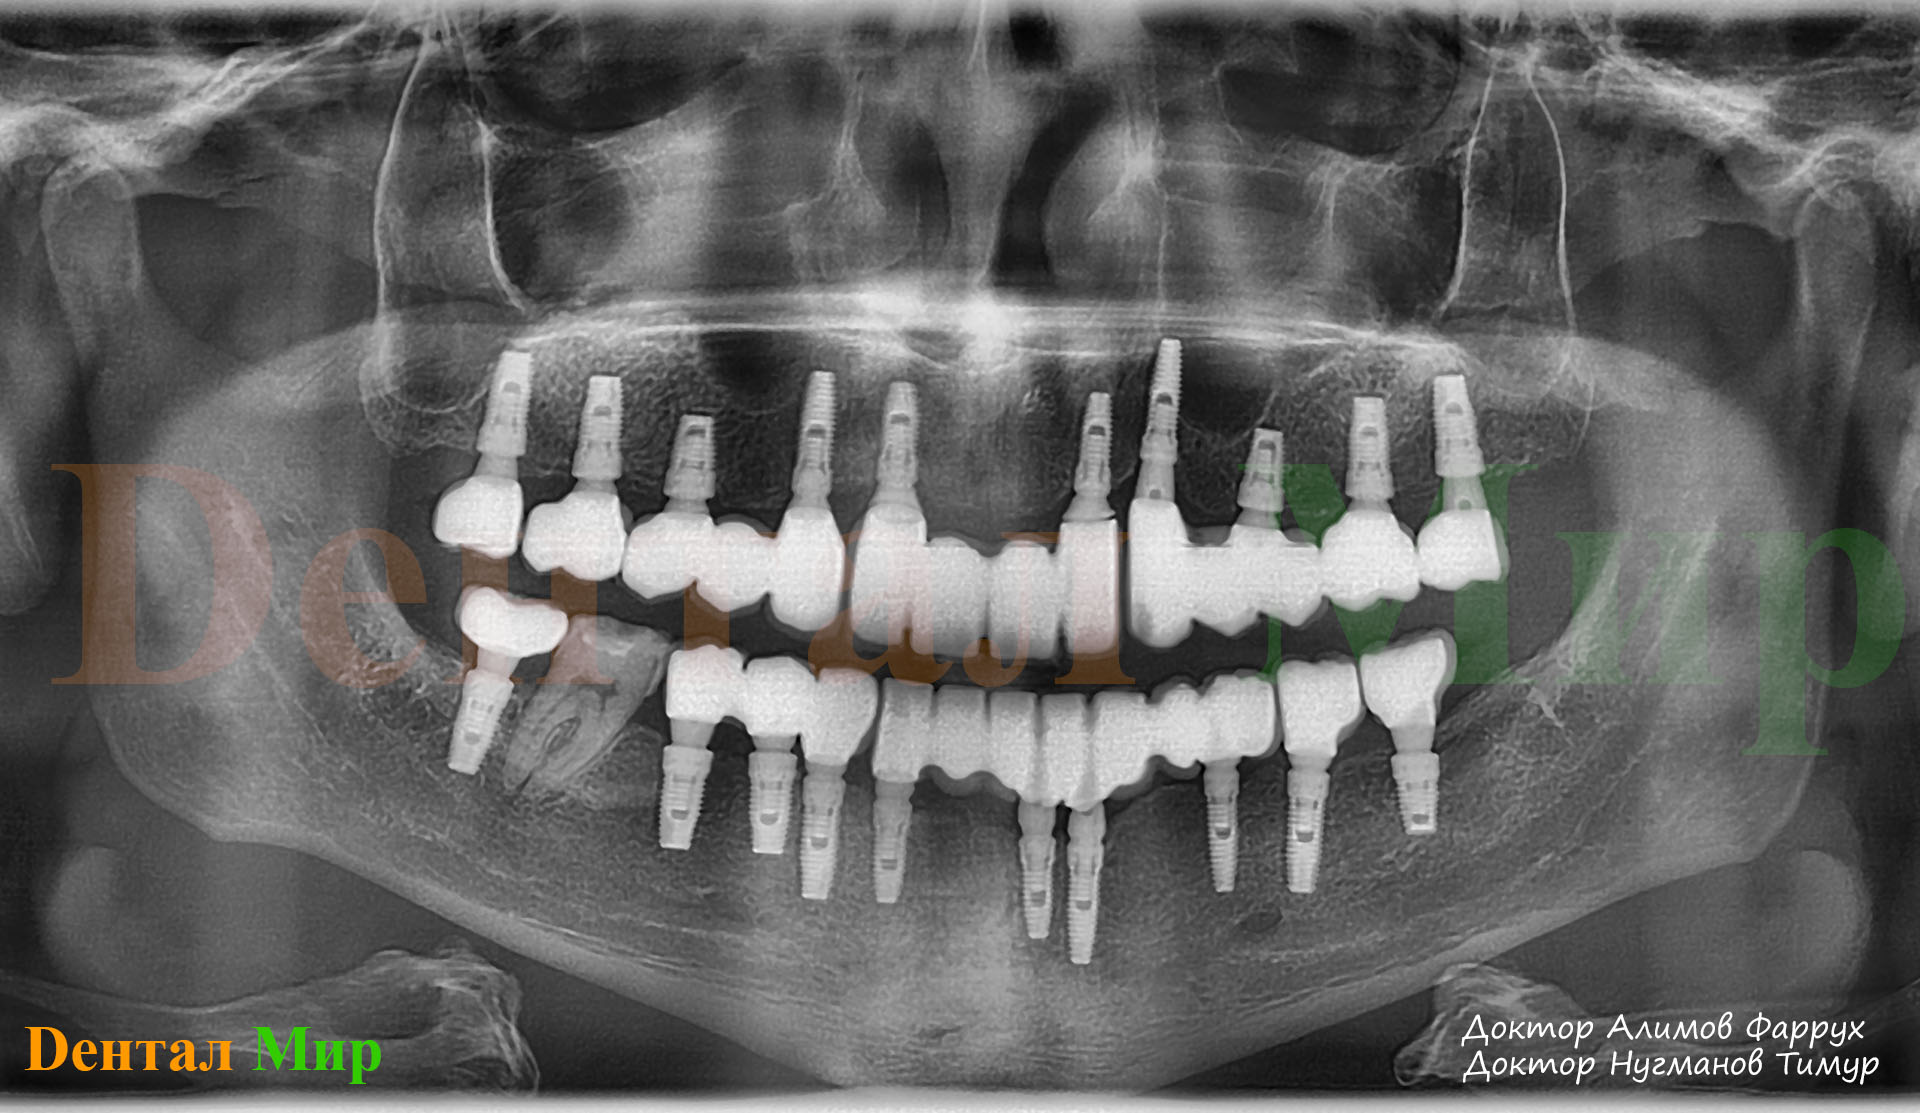

Исследование на рентгене после имплантации зубов

Раздел: Снимки-откровения